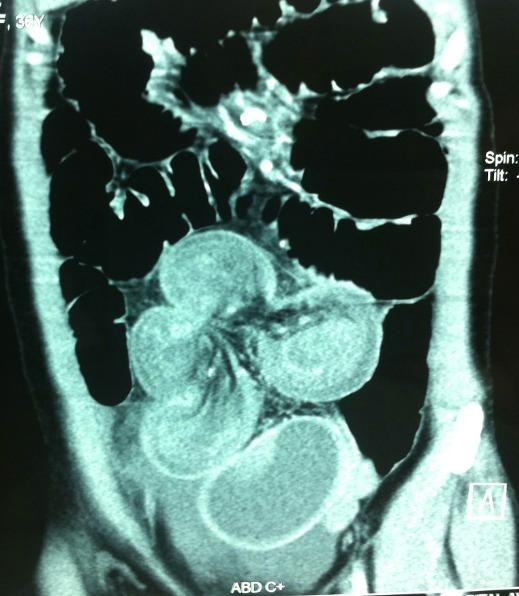

The primary malignant tumors of the small bowel are rare, representing 1 to 1.4% of all gastrointestinal tumors. We report a case of a 33 year-old women, admitted to our emergency department of visceral surgery for acute abdomen. The clinical examination revealed diffuse abdominal distension, defenseless, the hernia orifices were free and the rectal examination was normal. The biological test showed no hydro electrolytic disorders with normal hemoglobin and normal renal function. The abdominal CT-Scan showed signs of bowel obstruction due to a volvulus with intussusception without ischemia. The patient was operated urgently; the exploration has revealed a small bowel obstruction in the ileum with volvulus, an intussusceptum associated with a retractile mesenteritis, and the hepatic exploration found no metastases. The patient underwent a bowel resection taking away the intussusceptum with the infiltrated mesentery. The postoperative course was uneventful. The pathological result has proved a well-differentiated neuroendocrine tumor with five free nodes. Through this observation, we aim to highlight that an obstruction of small bowel with volvulus and intussusception could be exceptionally due to a neuroendocrine tumor, this complication has enabled a relatively early diagnosis in the absence of metastases and a 6-month follow-up without recurrence is a demonstration.